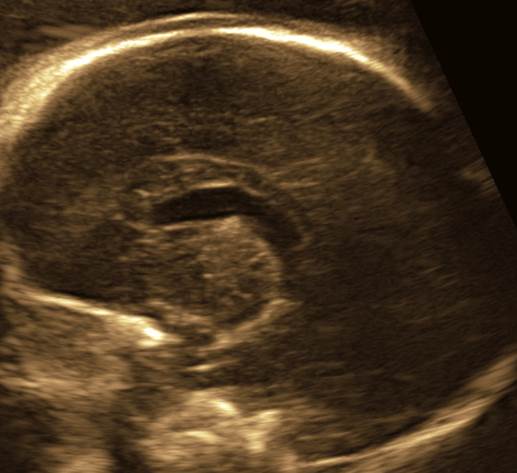

- Какие аномалии перед вами?

- Попытайтесь описать все, что не нравится. Прогноз?

- Срок 25 недель

Ответ на вопрос 7

- Мозолистое тело аномально, оно дисгенезировано.

- Отмечается повышенное содержание церебро-спинальной жидкости в передних рогах и субарахноидальном пространстве.

- Мозг уменьшен в объеме – микроэнцефалия.

- Анормальное строение (сглаженность) сильвиевых борозд.

- Прогноз, без сомнений, не благоприятный.